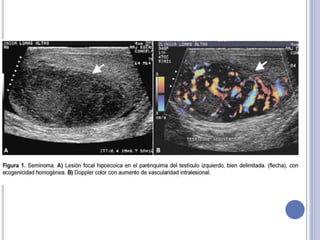

ECOGRAFÍA

 Permite detección de neoplasias

no sospechadas por el examen.

 Descarta diagnóstico diferencial.

 Permite el examen simultáneo

del testículo contralateral.

 Pesquisa la presencia de

microcalcificaciones.

 Sensibilidad de 95% pero con

una especificidad menor.

Seminomas: sólidos, hipoecogénicos,

homogéneos, bien delimitados y

relativamente bien vascularizados.

Teratocarcinomas: mixtos, heterogéneos,

con áreas quísticas y con abundante

vascularización.

Tumores embrionarios: calcificaciones

focales irregulares y escasa vascularización.

Tumores mixtos hacen confuso el patrón

ecográfico.

Tumores benignos: Raros, hiperecogénicos

(especialmente los que derivan del estroma,

como lipomas y fibromas).